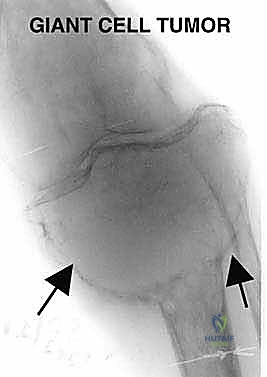

* ورم الخلايا العملاقة (Giant Cell Tumor - GCT): هو المثال الأبرز في هذه الفئة. ينشأ غالباً في نهايات العظام الطويلة بالقرب من المفصل (مثل الظنبوب القريب). في الحالات المتقدمة التي يدمر فيها الورم القشرة العظمية وسطح المفصل، يصبح الاستئصال الكامل وإعادة البناء بالطرف الصناعي هو الخيار الأمثل لمنع عودة الورم (Recurrence).